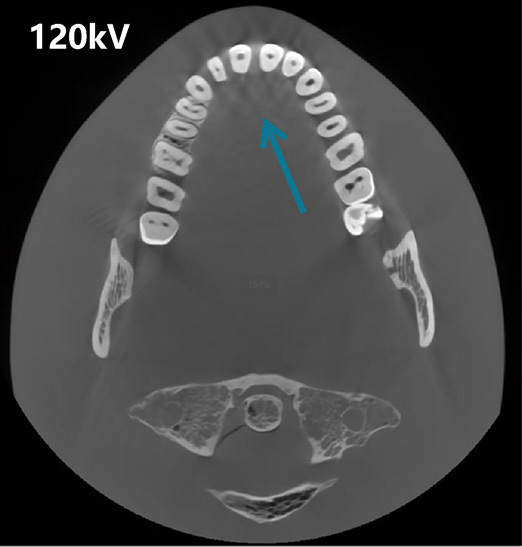

Generador de Alto Voltaje de 120 kV

Imágenes de alta energía para una salida estable y ruido reducido, asegurando claridad incluso en anatomías desafiantes.

Reducción de Artefactos Metálicos (MAR)

Reduccion de Ruido y Correccion de Endurecimiento del Haz

Corrección Geométrica